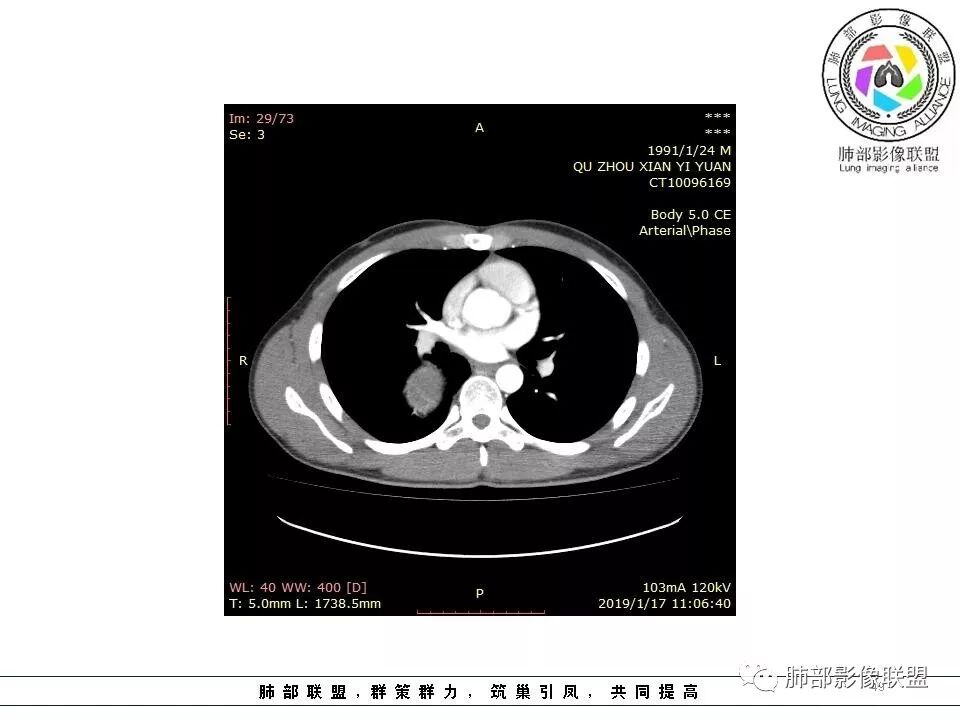

后纵隔脊柱旁占位性病变,疾病谱有神经鞘瘤,sft,节细胞瘤,髓外造血。此例有胸膜尾征,蛇纹征 ,延迟强化。考虑胸膜孤立性纤维瘤。看到有供血动脉,但不知道是哪里的血管。

后纵隔类圆形新生物,边缘光滑,胸膜尾征明显,贴近脊柱,蛇纹,血供丰富,考虑后纵隔软组织肿瘤,具体类型看不出来,鉴别神经鞘瘤。

定位肺外。强化不均匀,散在血管。考虑sft,鉴别:神经鞘瘤,付节瘤,cd。鞘瘤有ab区,付节瘤高血压,cd强化,形态不支持。

病灶定位脏层胸膜,肺组织受挤压,有胸膜尾征,动脉期可见血管支配,考虑肺动脉供血,静脉期,强化增强明显,符合快进慢出特点,病灶内可见低密度区,考虑胸膜孤立纤维瘤。

右侧后纵隔脊柱旁占位,边缘光滑清晰,内侧肺组织受压,外侧可见胸膜尾征,增强持续强化,并可见蛇纹血管征。考虑SFT

右肺占位,跨越上叶后段、下叶背,边缘光滑,瘤肺界面清,见肺压缩缘(线样不张`强化),见胸膜尾征,胸膜下脂肪未见明显增厚,肋骨丶脊柱未见侵袭及受压,渐进性丶地图样强化,冠状位似见体循环供血

诊断:SFT(来源壁层胸膜?一般小于20%)

鉴别:神经源性(鞘瘤)、LCD、肉瘤丶孤立性间皮瘤

3.相邻椎间孔未见扩大,也未见块影延入椎管,易起自于神经根的鞘瘤似乎找不到支持点。

可惜未提供矢状位骨窗图像,如在肋骨内下缘观察到压迹有助于肋间神经的鞘瘤的判断,这是因为二者之间密切的毗邻关系。

4.静脉期轻度不均匀强化,注意不是环形强化,亦未见明确的“AB区”,这点也不支持神经鞘瘤。临床及病灶轻度强化都不支持副节瘤。